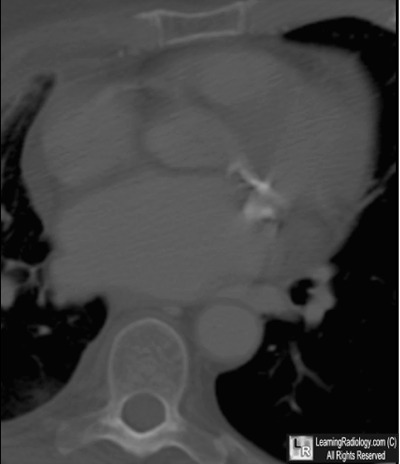

Additional Images - Axial CT Scan of Heart

Axial CT Scan of Heart

5. Mitral Stenosis

Mitral Stenosis